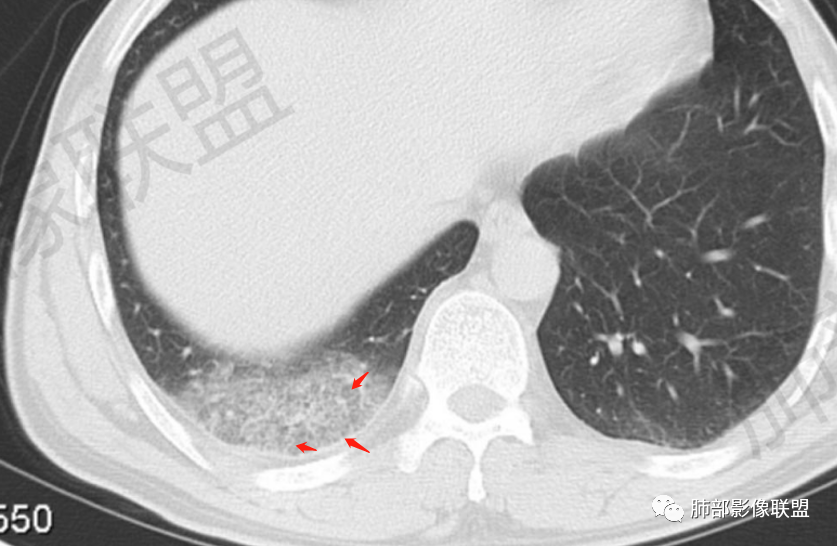

一切∮随缘:右肺肺尖段多发结节片状高密度影,部分伴有反晕征,边界欠清楚,部分伴有纤维索条,支气管显示欠佳,小叶间隔增厚,周围血管束增粗,(考虑结核可能)右肺下叶胸膜下片状磨玻璃影,与胸膜相贴,与肺组织交界面清楚,实性偏少,考虑:肺栓塞?病毒?OP?

王秀仙:右肺上叶可见结节及斑片影,部分呈反晕征,边缘清晰,右肺下叶后基底段胸膜下磨玻璃样实变影,呈扇形,内部见细网格,右肺上叶考虑结核。右肺下叶考虑肺栓塞,鉴别病毒肺炎。

小兜:男,47岁,胸闷气短入院,一天前无明显诱因胸闷气短伴呼吸困难,夜间出现右侧胸痛,与呼吸及体位有关,曾有一次痰中带血。CT示右肺上叶尖段多发结节,条索影,可见树芽征及反晕征。右肺下叶胸膜下片状密度增高影,宽基底与胸膜相连,成扇形。综合考虑右肺上叶尖段结核可能;右肺下叶肺栓塞?病毒性肺炎?

琦遇:右肺上叶结核基本明确,考虑活动性,有钙化、反晕征、结节、斑片、纤维索条;右肺下胸膜下GGO,内大小网格,胸膜增厚,患者胸痛,咯血,首先考虑PE,下一步增强CTPA以明确

微微笑:右肺上叶斑片、结节、索条影,边缘较清晰,见反晕斑片,考虑结核。右肺下叶宽基底磨玻璃影,网格样改变,胸膜增厚,结合病史,考虑栓塞。

小锁:中年男性患者,急性起病,胸闷气喘伴有胸痛,低热,低氧,白细胞增高。CT:右肺上叶斑片状稍高密度影,粟粒样树芽征,有钙化,考虑继发性结核;右肺下叶肺动脉增粗,溶冰征,提示血管来源病变,结合临床病史,考虑肺栓塞。

后基底段,胸膜下,这个没问题吧

我们看看病变的形态、密度、边缘、内部改变

GGO密度

边缘不清

可惜没有重建,楔形?

细网格明显

支气管通畅,壁增厚

血管增粗

南边:首先应该不是气道来源的病变,气道的应该是小气道病变为主。

血管来源的:梗死要考虑